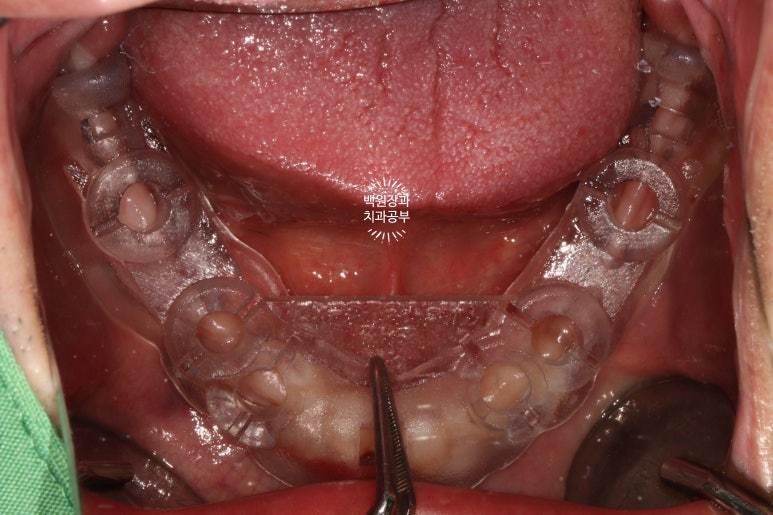

약 2주가 지난 시점에, 아래턱 임플란트 수술도 진행!

아래턱 임플란트도 오스템 임플란트의 네비게이션 임플란트 시스템인,

오스템 원가이드를 이용한 가이드 서저리로 시행하였습니다. 보시면 여섯개의 임플란트 수술이 예정된 것을 확인할 수 있죠.

수술 하기 전 다시 봐도 정말.. 너무너무 얇은 잇몸뼈를 보실 수 있습니다.

칼 ridge라고도 부르는데... 손이 베일 것 같이 얇은 뼈 높이..

이런 경우 얇은 잇몸뼈는 일부 삭제 후 두꺼운 뼈 부위에 뼈이식을 하면서 임플란트를 위치시키게 됩니다.

나는 임플란트 장인이라는 생각을 갖고, 혼을 담아 임플란트 수술을 해드렸습니다.....

앞쪽에 식립되었던 4개의 임플란트는 역시나.. 얇은 잇몸뼈 밖으로 일부를 드러내고 있는 모습을 볼 수 있었구요..

이번에도 역시 덴티움 社의 합성골인 osteon III와 주변에서 채득했던 자가골을 이용하여 충분한 뼈이식을 해드렸습니다. 비용이 다소 추가되지만, 성공적인 뼈이식을 하기 위해서 같은 회사의 '흡수성 콜라겐 차폐막'은 반드시 사용되어야 합니다.

이것이 GBR (guided bone regeneration)의 기본 원리입니다.